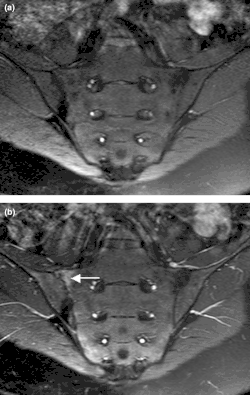

| Magnetic resonance images of sacroiliac joints. Shown are T1-weighted semi-coronal magnetic resonance images through the sacroiliac joints (a) before and (b) after intravenous contrast injection. Enhancement is seen at the right sacroiliac joint (arrow, left side of image), indicating active sacroiliitis. This patient had psoriatic arthritis. Sacroiliitis is a condition caused by inflammation within the sacroiliac joint.[1] This joint is located where the base of the spine, known as the sacrum, and the pelvis, known as the ilium, intersect. "Itis" is a Latin term denoting inflammation.[2] | |